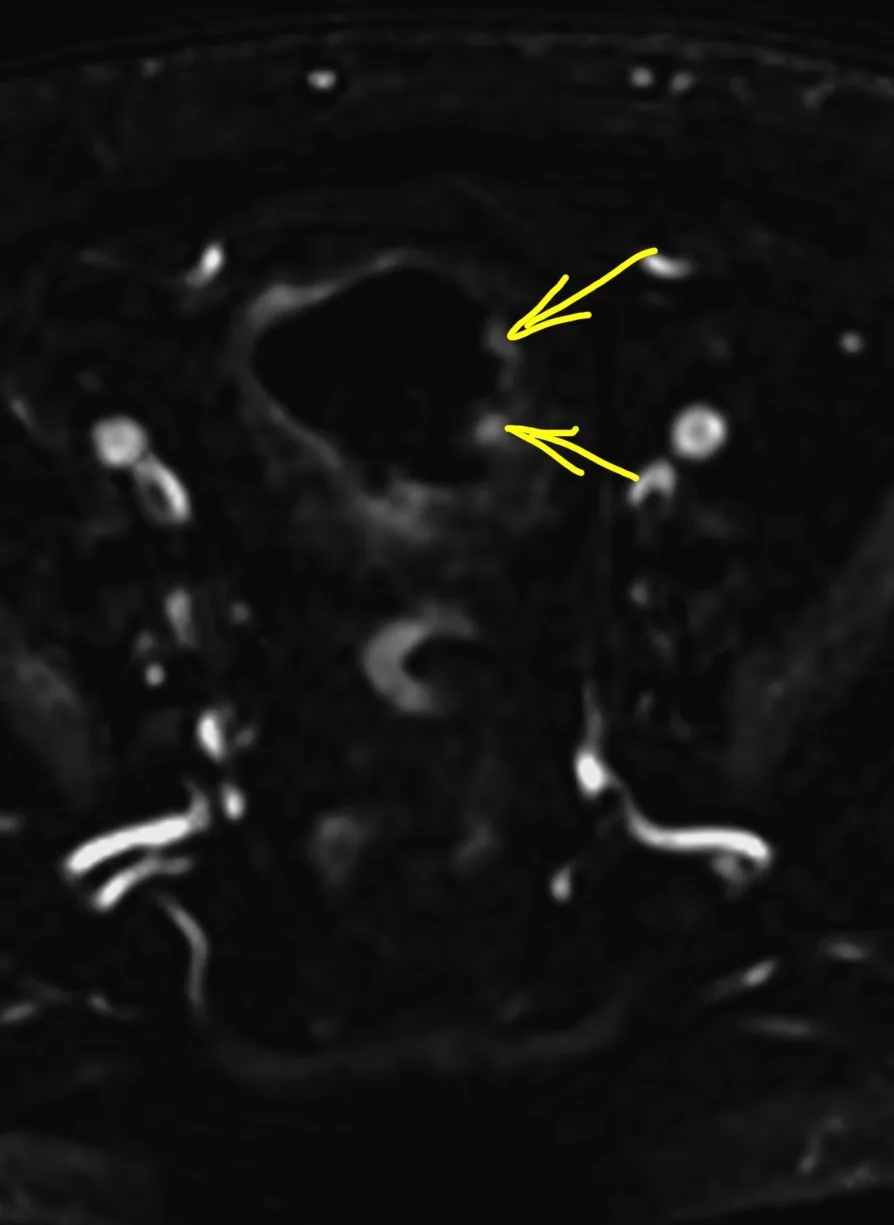

Менингиомы иногда не ходят одни. А по две, три и больше. Самая крупная слева в ЗЧЯ - хорошо видно место, из которого она растет: фокальные утолщения кости по краям и плоское основание опухоли (стрелки).